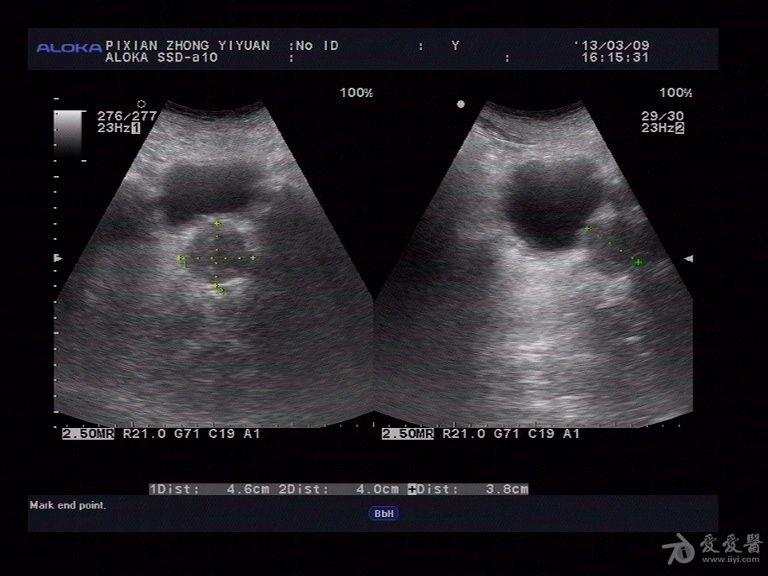

膀胱憩室一例,希望大家喜欢

图片尺寸640x480